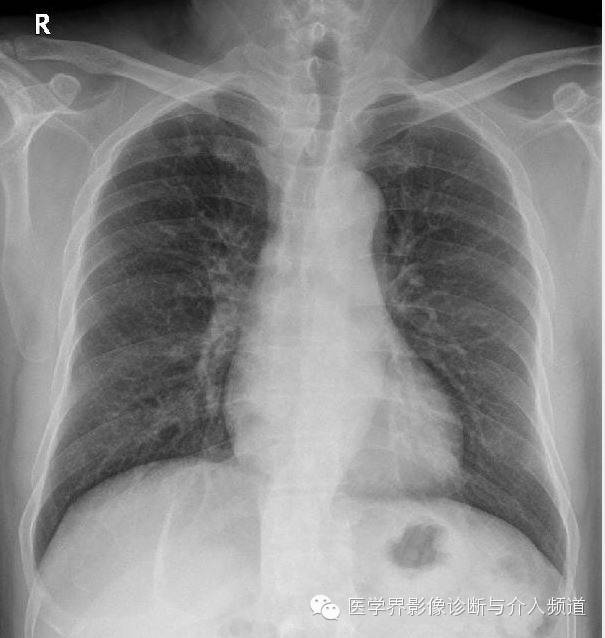

治疗后

CT显示右肺上叶实性团块病灶内不规则空洞形成,周围可见GGO,右侧胸腔少量积液。患者外周血嗜酸性粒细胞增多和Pw抗体阳性。治疗后X线平片显示右上肺结节影缩小。治疗前X线片显示病灶位于右肺上野,右侧肋膈角变钝。此外,X线平片示主支气管节段性偏心性狭窄,这是由于胸内甲状腺肿外在压迫所造成。